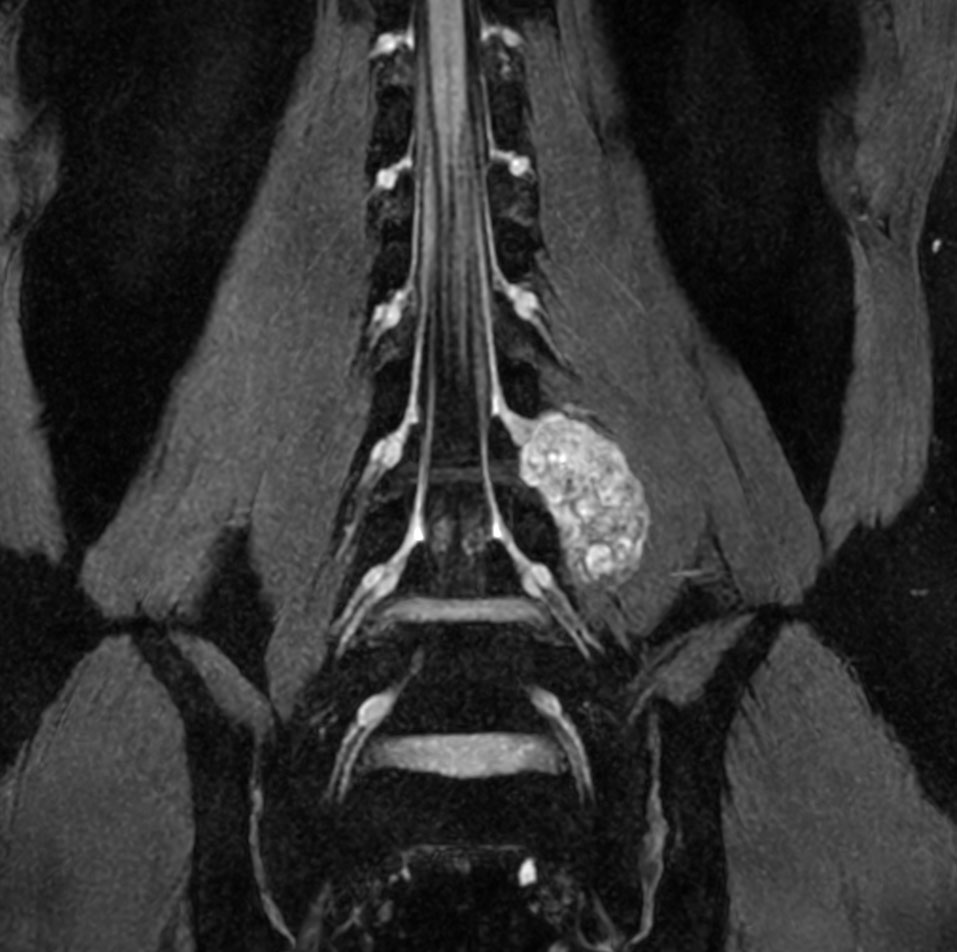

Neurography schwannoma (Compressed SENSE)

Patient with a lumbar neurography schwannoma.